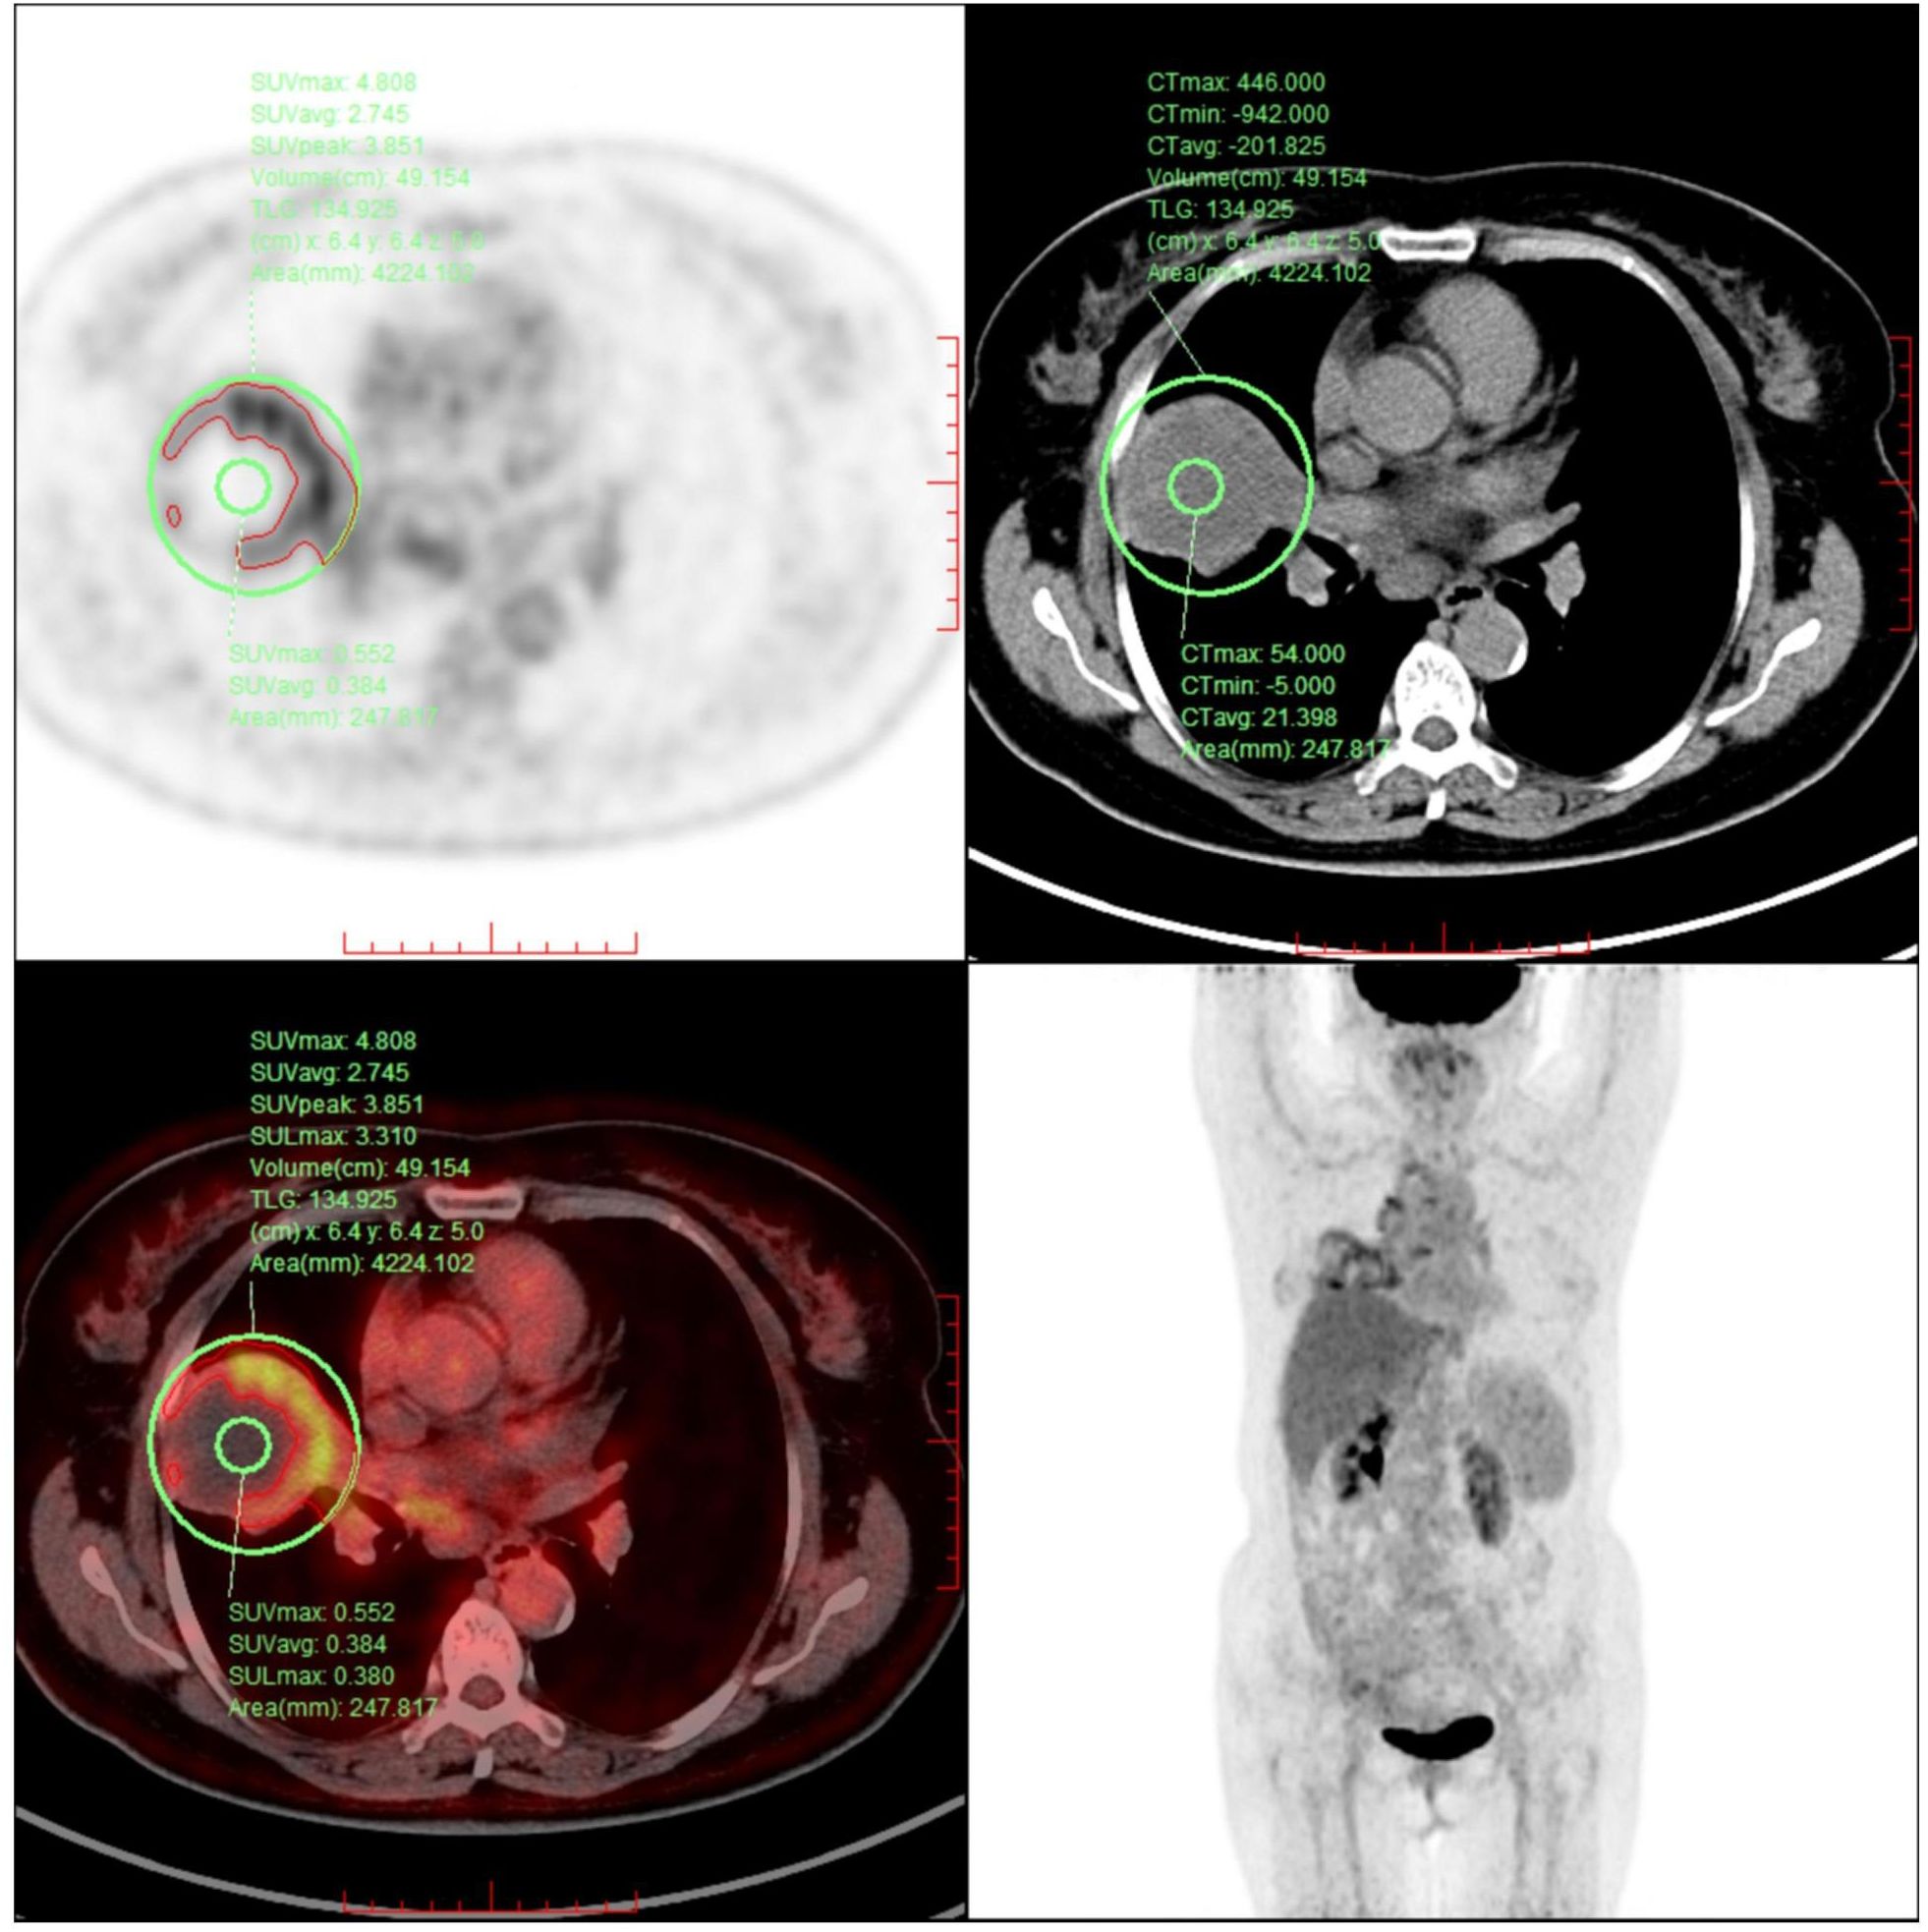

Urachal carcinoma is a rare and aggressive malignancy with limited treatment options, particularly in the metastatic setting. Standardized therapeutic protocols are lacking. This case report describes a 62-year-old female patient who developed pulmonary and mediastinal lymph node metastases more than four years after surgical resection of urachal carcinoma. For this case, a combined regimen of Spatially Fractionated Radiotherapy (SFRT), CapeOX (capecitabine plus oxaliplatin) chemotherapy, and bevacizumab targeted therapy was developed. The treatment course was complicated by grade 4 hematologic toxicity and radiation-induced esophagitis, both of which were successfully managed. To our knowledge, this represents the first documented application of SFRT in urachal carcinoma. Although significant tumor shrinkage was not observed, the patient achieved symptomatic relief, metabolic remission, and stable disease during follow-up.